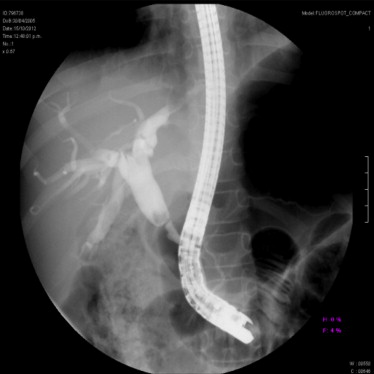

Dilatación de estenosis esofágica y colocación de prótesis

Las prótesis metálicas autoexpandibles (PMA) están formadas por una malla cilíndrica de metal cortada por láser que ejerce su fuerza autoexpansiva hasta llegar a su diámetro máximo, cuando se liberan de un dispositivo donde están comprimidas, con el fin de recuperar la luz intestinal de un área estenosada (obstrucción benigna o maligna).

Todas las prótesis están comercializadas en una variedad de longitudes y diámetros o con extremos (copa) más anchos para facilitar el anclaje de la prótesis y evitar la migración.